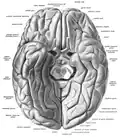

![]() Hemisferio cerebral izquierdo, vista inferior: localización del giro recto en la superficie orbital. | ||

El giro recto es una circunvolución del cerebro. Se encuentra en la cara orbitaria del lóbulo frontal del cerebro, entre el surco olfatorio o cisura olfativa y el borde medio.[1][2]